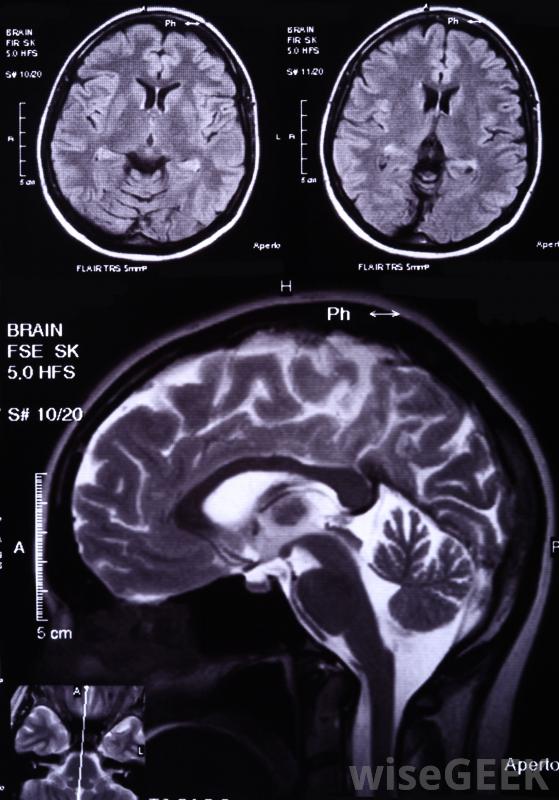

什么是膠質母細胞瘤(Glioblastoma)?

膠質母細胞瘤是一種惡性的腦瘤,通常是致命的,對這種腫瘤的治療主要集中在姑息治療上,而不是試圖治愈病人。這種腫瘤是一種星形細胞瘤,意味著它發生在大腦中被稱為星形膠質細胞的細胞中,它是最常見的腦瘤形式。幸運的是,腦瘤一般情況下非常罕見,約2%的癌癥發生在腦部。視力問題可能是膠質母細胞瘤的癥狀與其他星形細胞瘤一樣,當大腦細胞中的基因信息受到破壞,導致細胞無法控制地繁殖時,膠質母細胞瘤就開始形成了,腫瘤的生長包括一個壞死區域,周圍有分化不良的星形膠質細胞。隨著腫瘤的生長,患者可能會出現頭暈、惡心、意識混亂、平衡困難、視力問題和其他神經系統問題隨著腫瘤的生長,患者可能會出現頭暈、神志不清和其他神經系統問題。醫生可以診斷為膠質母細胞瘤通過醫學影像學研究來觀察大腦,并對其生長過程進行生物切片以找出它是什么當病理學家檢查活檢標本時,他或她可以確定哪些類型的細胞參與其中,以及腫瘤的侵襲性有多強。膠質母細胞瘤也被稱為IV級星形細胞瘤,指的是腫瘤起源的細胞類型,以及這些腫瘤非常具侵略性的事實膠質母細胞瘤通常不會轉移到身體的其他部位,這使得腫瘤的治療主要集中在防止腫瘤生長上膠質母細胞瘤通常不會轉移到身體的其他部位,這使得腫瘤的治療主要集中在防止腫瘤生長,并使病人感到舒適。建議手術切除盡可能多的腫瘤,化療和放療可以延長患者的壽命,對于膠質母細胞瘤等疾病,新的治療方法不斷開發,改善預后,延長壽命。治療膠質母細胞瘤通常側重于姑息治療,男性最有可能患上這種癌癥,而且通常發生在50歲以上的人身上。這種癌癥似乎有一些遺傳成分,它也可能與環境中的輻射有關當被診斷為膠質母細胞瘤時,患者應該向醫生詢問關于預后的真實意見,他們可能會想談談臨終關懷,這樣他們就可以在他們仍處于高度功能狀態的情況下對自己的護理做出決定。與所愛的人談論對護理和治療的具體愿望也是至關重要的,患者可能會考慮創建一個醫療代理,在無法溝通的情況下確保愿望得以實現的人。可以進行活檢,以確定與膠質母細胞瘤有關的細胞類型平均而言,被診斷為膠質母細胞瘤的患者壽命不到一年。醫學影像學研究可用于診斷膠質母細胞瘤腦瘤化療和放療有助于延長膠質母細胞瘤患者的壽命。